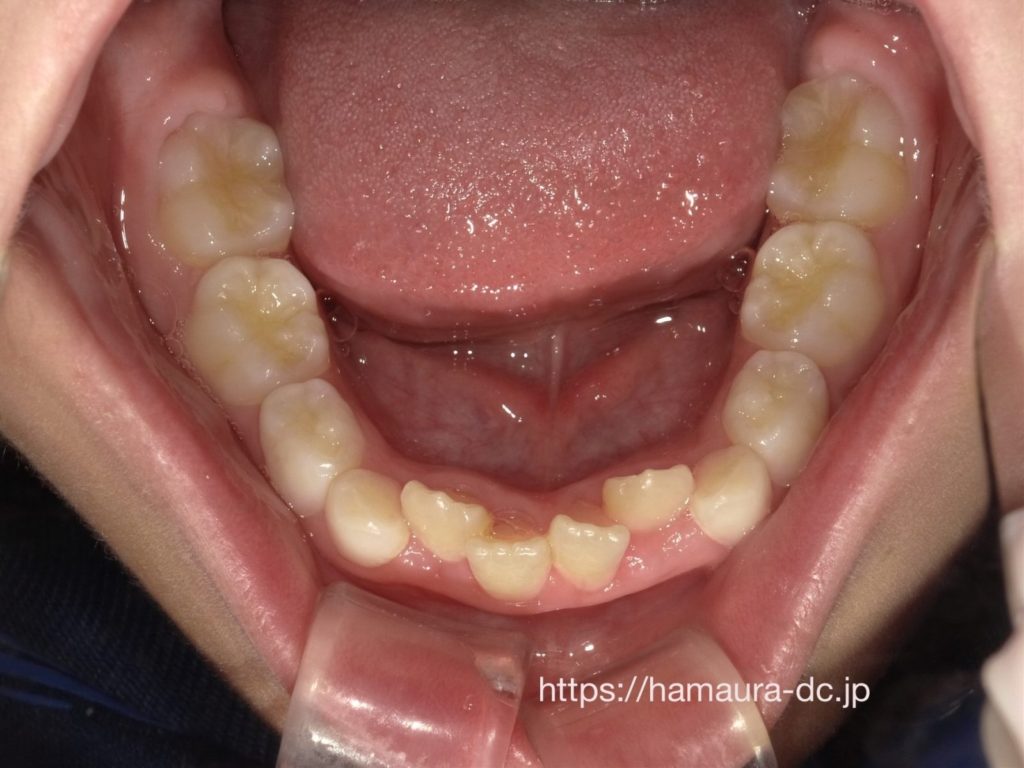

この症例の状態

このお子さまは

・下の前歯の重なりが強い

・上の前歯も曲がって生えている

状態でした

治療後

顎を広げることで

👉 前歯の重なりが改善し

👉 歯が並ぶスペースが確保されました

現在は安定した歯並びを維持しています

治療期間について

この症例では

👉 7歳から治療を開始し、約3年で改善しました